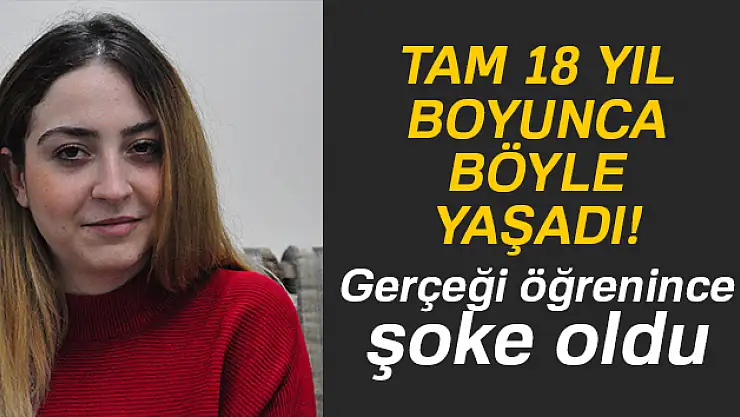

18 yıl boyunca böyle yaşadı

Manisa'nın Soma ilçesinde 3 yaşındayken olduğu bademcik ameliyatında boğazında ameliyat iğnesi unutulan 21 yaşındaki Meltem Cansız, o iğneden tam 18 yıl sonra geçirdiği başarılı bir operasyonla kurtuldu.Soma Devlet Hastanesi'nde bademcik şikayetiyle 1999

Manisa'nın Soma ilçesinde 3 yaşındayken olduğu bademcik ameliyatında boğazında ameliyat iğnesi unutulan 21 yaşındaki Meltem Cansız, o iğneden tam 18 yıl sonra geçirdiği başarılı bir operasyonla kurtuldu.

Soma Devlet Hastanesi'nde bademcik şikayetiyle 1999 yılında ameliyat olan Meltem Cansız'ın boğazında iğne unutuldu. 18 yıl boyunca boğazında iğne ile yaşayan ve şu anda 21 yaşında olan Meltem Cansız'ın tüm hayatı acı ve ağrılarla geçti. Boğazındaki iğnenin acıları günden güne yıldan yıla artan Meltem Cansız, 11 yıl sonra 14 yaşında iğnenin fark edilmesiyle Ege Üniversitesi'nde bıçak altına yattı ancak ameliyatı başarısız geçti.

Lise öğreniminden sonra sağlık sorunları nedeniyle üniversiteye hazırlanamayan Meltem Cansız, acılarına rağmen yılmadı sabırla bekledi ve geçirdiği başarılı ameliyatla o iğneden 18 yıl sonra kurtuldu.

Boğazındaki iğneyle geçen 18 yılını anlatan Meltem Cansız, "3 yaşında geçirdiğim bademcik ameliyatında iğne boğazımda unutulmuş. Daha sonra iğneden dolayı 11 yıl sonra 14 yaşındayken kulak rahatsızlığım ortaya çıktı. Kafamın sağ tarafı ağrımaya başladı. Doktora gittik, hiçbir şey olmadığını söylediler. Sonrasında beni MR çekilmek üzere Akhisar'a yönlendirdi. Gecenin bir vakti MR'a girdim. Ancak bir türlü çekemediler. Benim üzerimde toka vs. metal bir şey olduğunu söylediler baktılar ancak bir şey yoktu. Üç yada dört defa MR'a girdim. Ancak bir türlü çekemediler. Sonra doktorumuz röntgene yönlendirdi. Röntgen görüntüsünde ameliyattan kalma bir çengelli iğnenin boğazımda olduğu görüldü. Bunun için beni Ege Üniversitesi'ne sevk ettiler. Burada doktorlar bu ameliyatı yapabileceklerini ancak riskinin çok olduğunu söylediler. Biz yine de kabul ettik. 1,5 saatlik operasyon geçirdim ancak iğneyi bulmadıklarını söylediler. 2 sene kadar araştırma yaptık. Birçok hastaneyle görüştük. Ancak ayağımda bir rahatsızlık meydana geldi. Ayağım için Ege Üniversitesi'ne gittik. Tekrardan beni ameliyat eden doktorumla görüştüm. 'Seni ben ameliyat ettim, tekrardan buna kalkışamam' dedi. MR'a da giremezsin dediler. 'Sen bununla yaşamayı öğren' en azından bunun için çabalama alınmaması daha iyi dediler. Ben daha genç bir kızım sonuçla bu iğneyle ömür boyu yaşayamazdım. Yaşanan bu olumsuzların ardından araştırmalarımız neticesinde en son İzmir'de özel bir hastaneye gittik. Oradaki doktorum Çağlar Çallı bey bana umut verdi. 'Bu iğneyi alacağız' dedi. İnancımı kaybetmedim, sonucun ne olacağını bilmeden girdim ben o ameliyata. Ölüm, felç olma riskim çok fazlaydı. 'Yaşayamayabilirsin' dediler, biz bile bile lades dedik. Sonucu da güzel oldu" dedi.

14 yıl sonra iğne unutulduğu ortaya çıktı

Baba Ahmet Cansız ise kızını 1999 yılında 3 yaşındayken bademcik sorunu nedeniyle Soma Devlet Hastanesi'ne götürdüğünü belirterek, "Bademcikleri nedeniyle çok sık hasta oluyordu. O günkü SSK'da doktorumuz ameliyat olması gerektiğini söyledi. Neticede ameliyat olduk. Ameliyat sonrasında aradan geçen süreçte kızım 17 yaşında geldiğinde yüzünde, sağ tarafında bir ağrının olduğunu, başının, kulağının ağrıdığını söyleyince kulak burun boğaz doktoruna gittik. İlaçlar verdi geçmedi, sonra bir daha gittik. Eklem arası bir iltihap olabilir diyerek MR istedi. Akhisar ilçesine MR çekilmeye gittik. Fakat bir türlü çekemediler. Daha sonra bir film çekildi ve iğne ortaya çıktı" diye konuştu.

"'İğne şah damarına yakın, kızın ölebilir' dediler"

Ege Üniversitesi'ne gittiklerini belirten baba Cansız, iğnenin şah damarına çok yakın olduğunun söylendiğini belirterek şunları söyledi: "Doktorlar çok tehlikeli bir ameliyat olacağını yanlış ya da en ufak bir hatada kızımızın bir tarafının felç kalabileceğini veya hayatını kaybedebileceğini söylediler. Biz bu riski göze alarak ameliyata müsaade ettik. Fakat iğneyi görüldüğü yerde bulamadıklarını söyleyerek alamadılar. Sonra İzmir Çiğli'de özel bir hastanede denedik. Kendisine binlerce kez teşekkür. Allah razı olsun. Çocuğumun boğazındaki iğneyi aldı. Dünyalar bizim oldu."